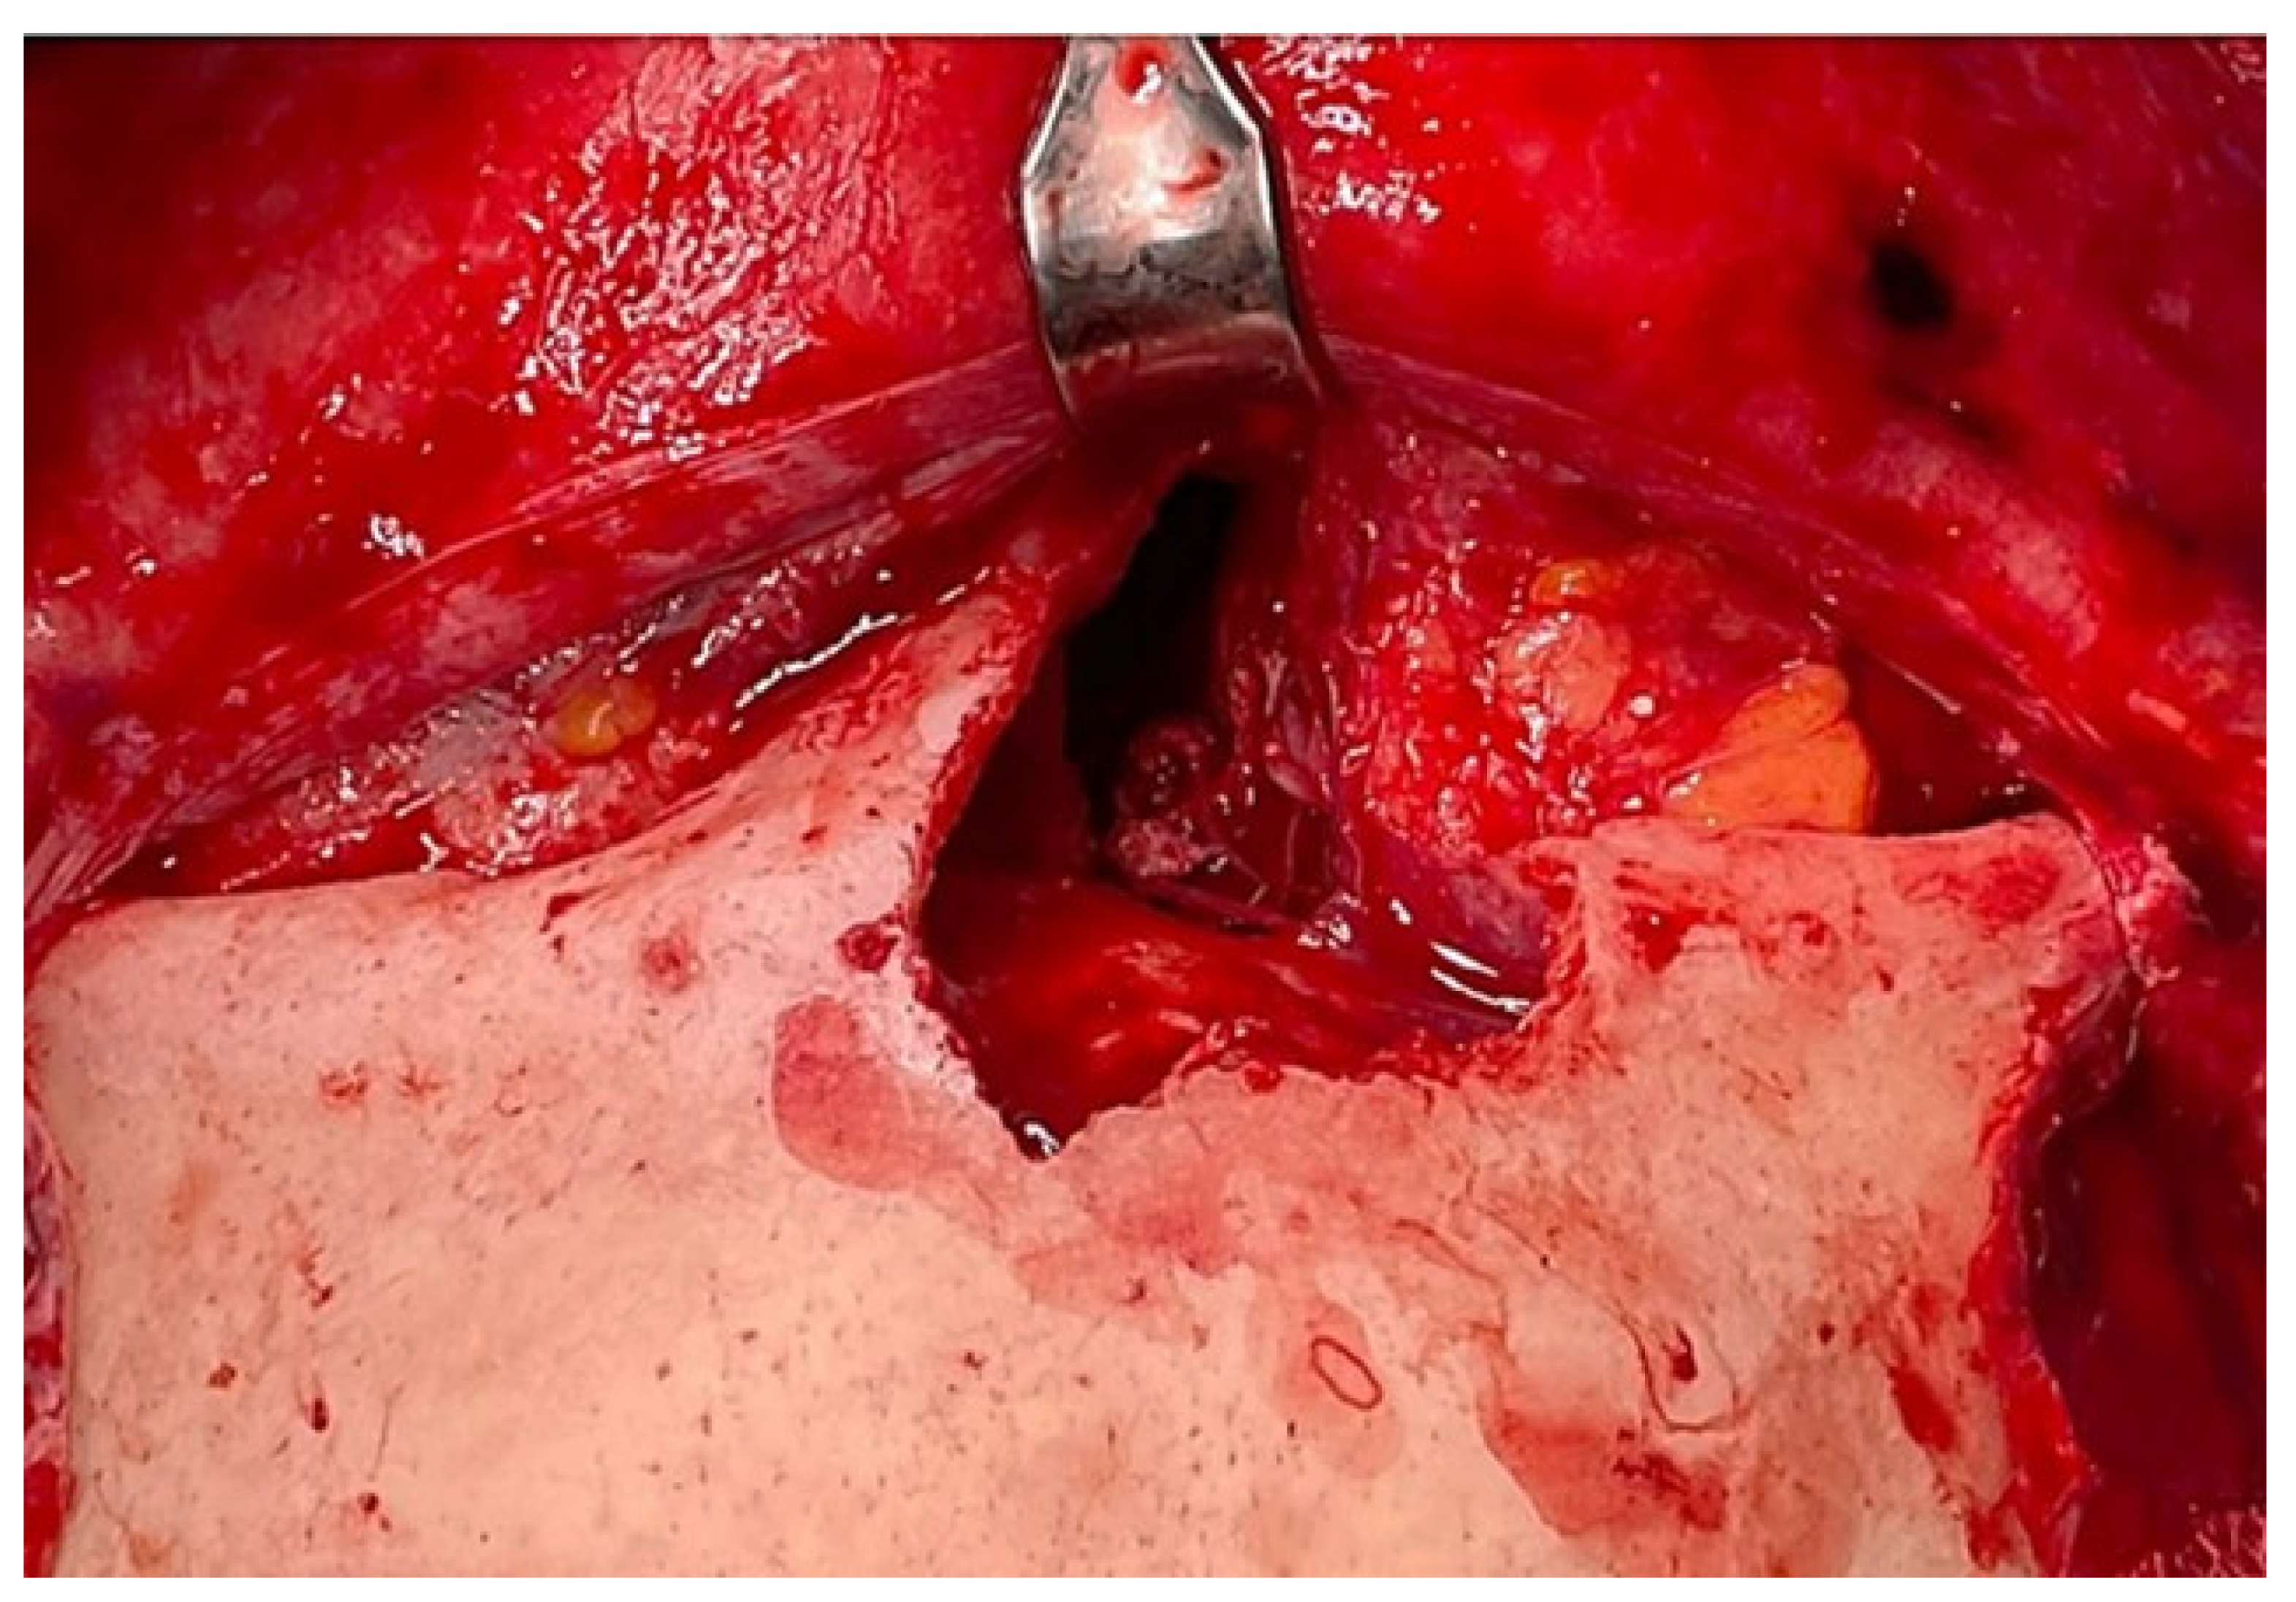

2. Presentation of Case